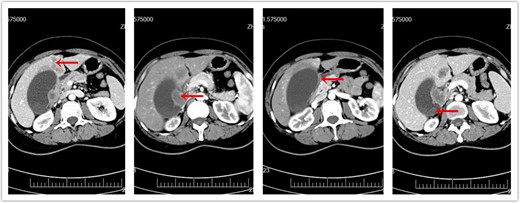

A 45-year-old female presented in July 2017 with intermittent right upper quadrant pain for 1 month. A computed tomography (CT) of the abdomen and pelvis with intravenous contrast revealed gallstones, a gallbladder mass, two liver masses in the left lobe, and portal lymphadenopathy (Fig. 1). The preliminary diagnosis was stage 4 GBC, for which the prognosis is poor and surgical treatment is usually not recommended. However, the patient strongly requested surgery hoping for a better outcome. We felt that the only chance for a cure in this young patient would be radical surgery to achieve an R0 resection. This complex surgery carried a high risk of complications. The patient understood the risks and chose to proceed with the surgery after signing informed consent.

CT of abdomen prior to surgery. (a) Metastatic liver masses. (b) Enlarged lymph nodes. (c) Invasion of duodenum. (d) Original gallbladder tumor.